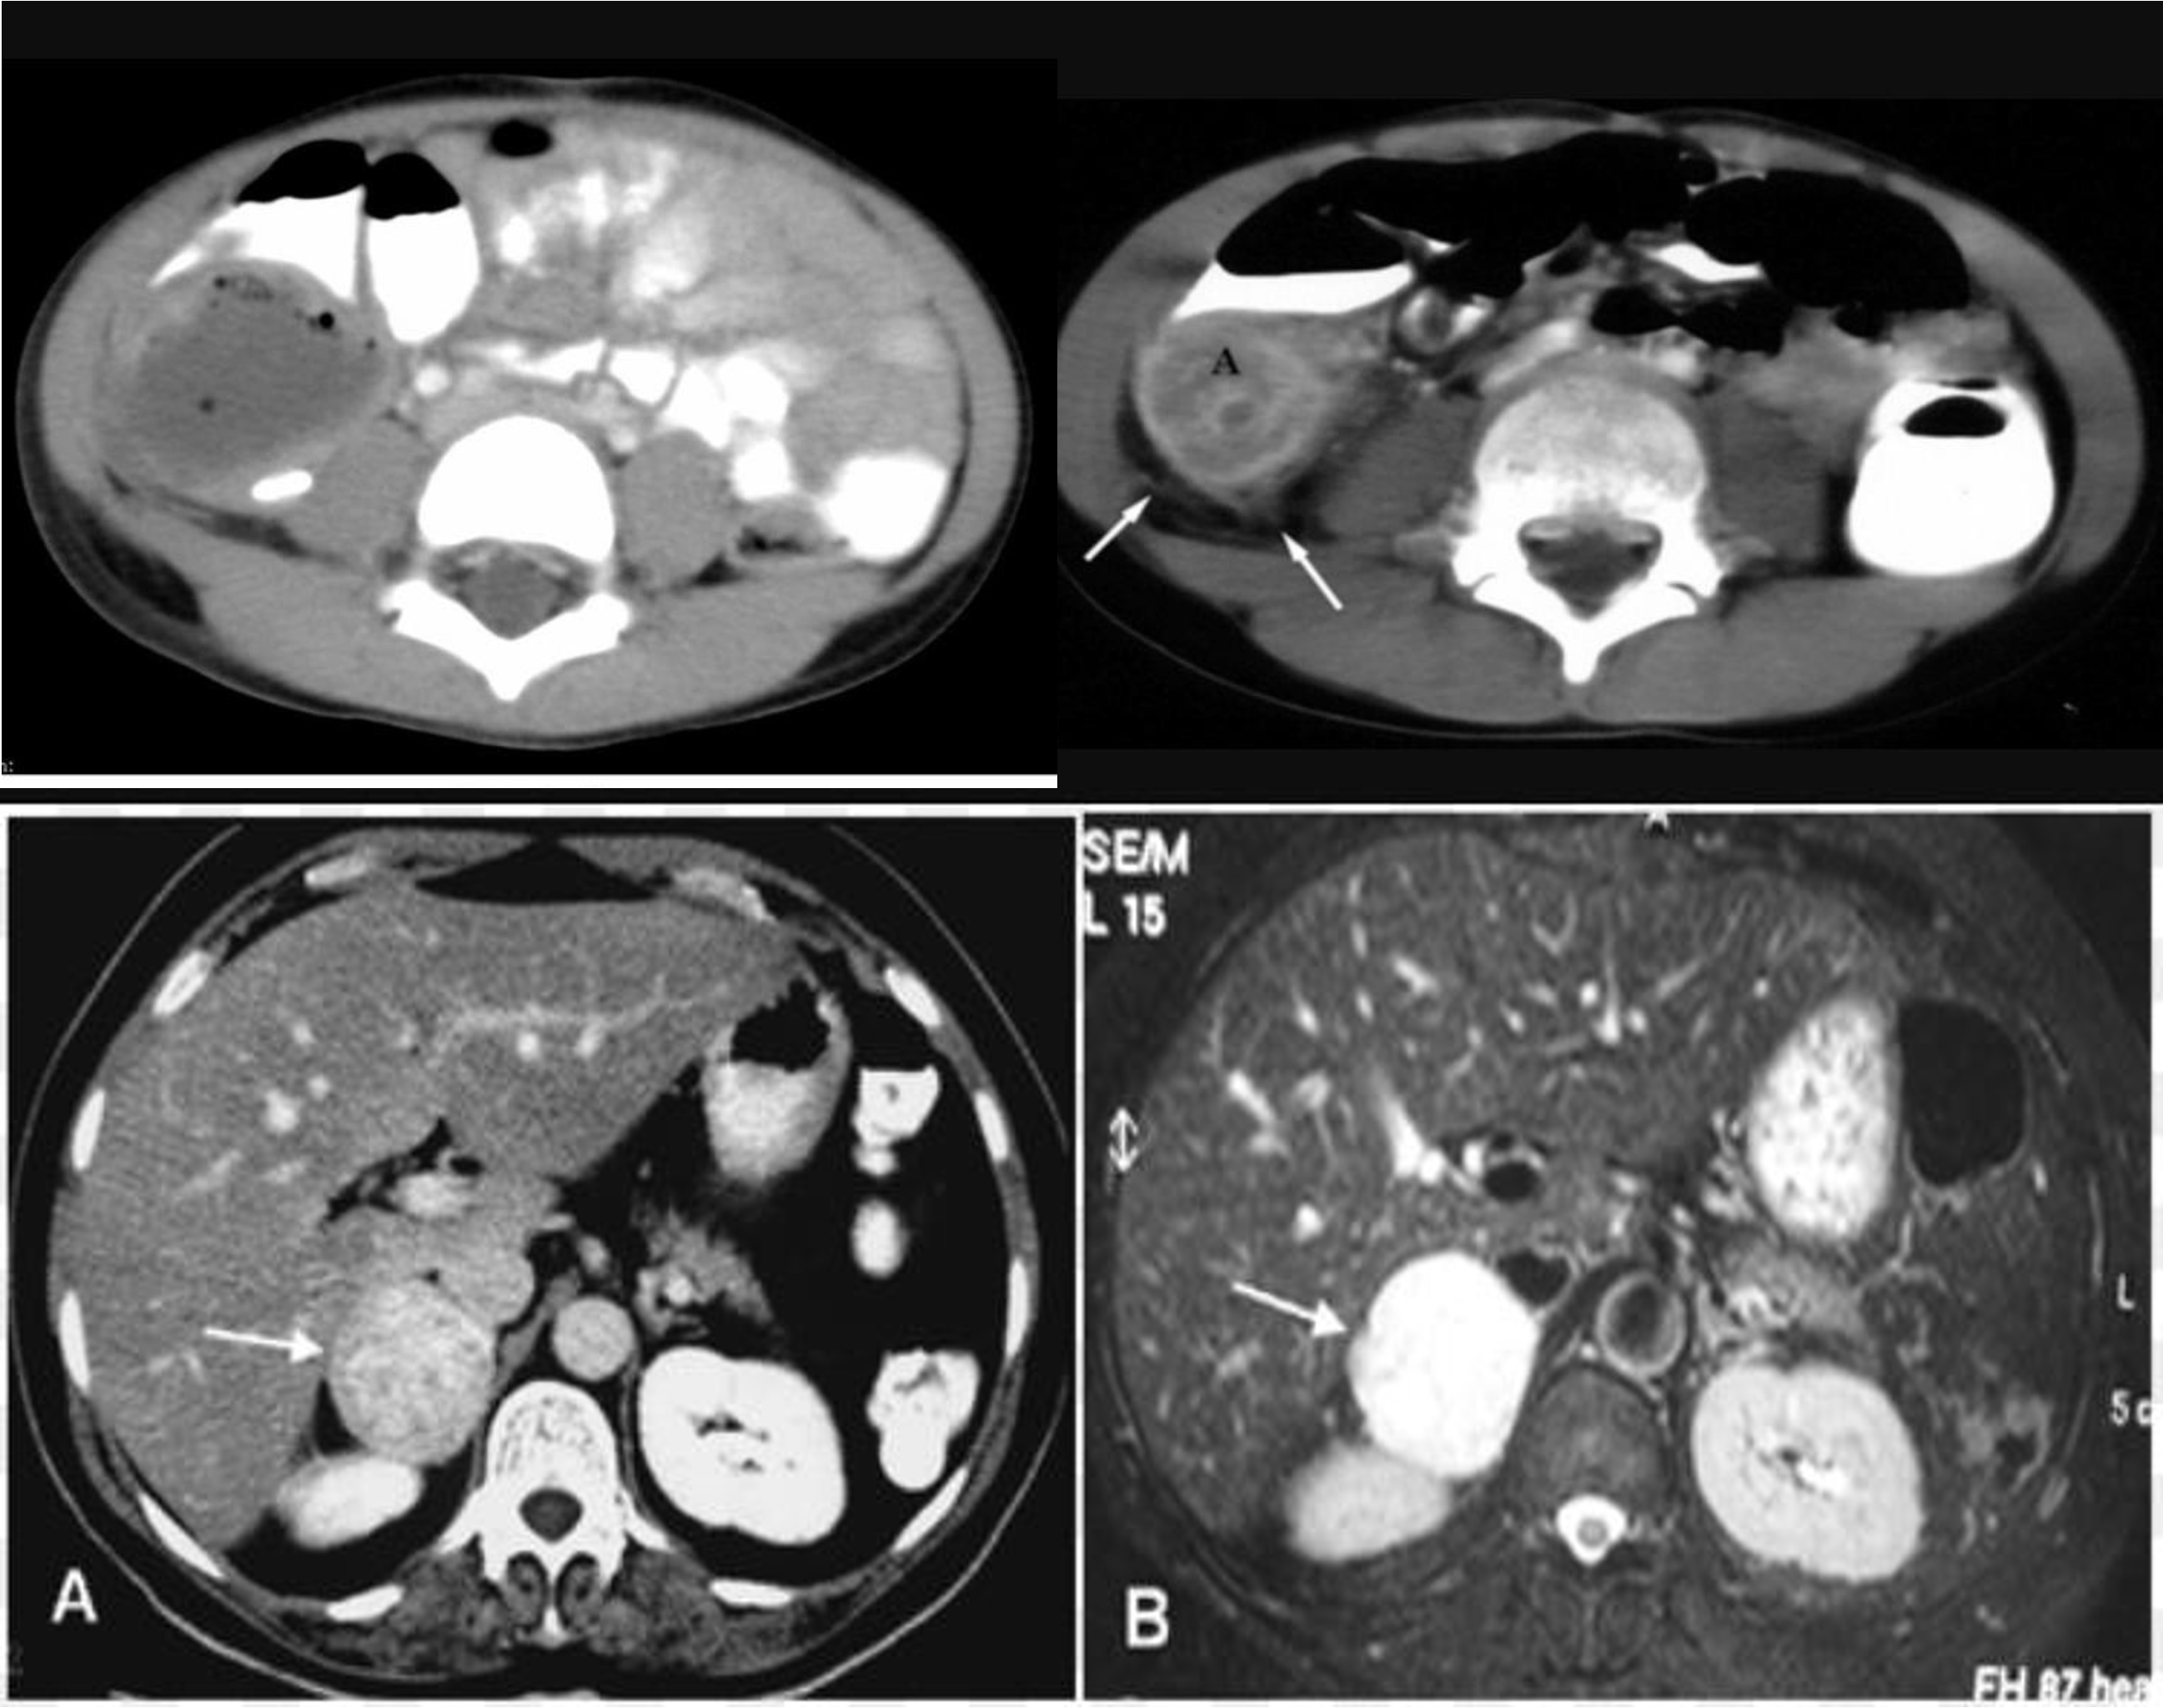

CT

- CBD + METASTESIS

- hypodense - spleenomegaly with splenic infarct

- patient compl anemia vomit - mass stomach - adenocarcinoma - stage 4 gastric cancer (cannon ball sign) - ct scan contrast porta

multiple lesion in liver due (Diff; cancer, multiple abcess pyogenic most likely)

Ireggular lesion peripheral enhancement - hypo in cent - febrile tender (liver abcess) - antibiotic + ct u/s guidance drainage

HCC, Cancer of liver, hepatic adenoma, FNH (with central scar star like)

- ct scan (hypodense lesion in liver well circumscribed single - most likely amoebic liver abcess)

- multiple … metastasis